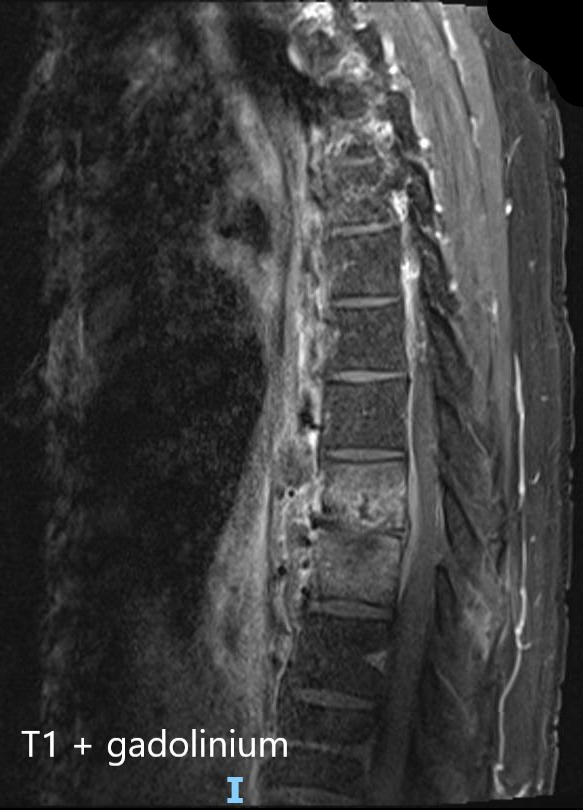

Il faut donc évoquer une pathologie rachidienne inflammatoire/infectieuse/tumorale avec syndrome de compression médullaire partiel se traduisant uniquement par une claudication médullaire : celle-ci correspond à un syndrome pyramidal, démasqué par l’effort.